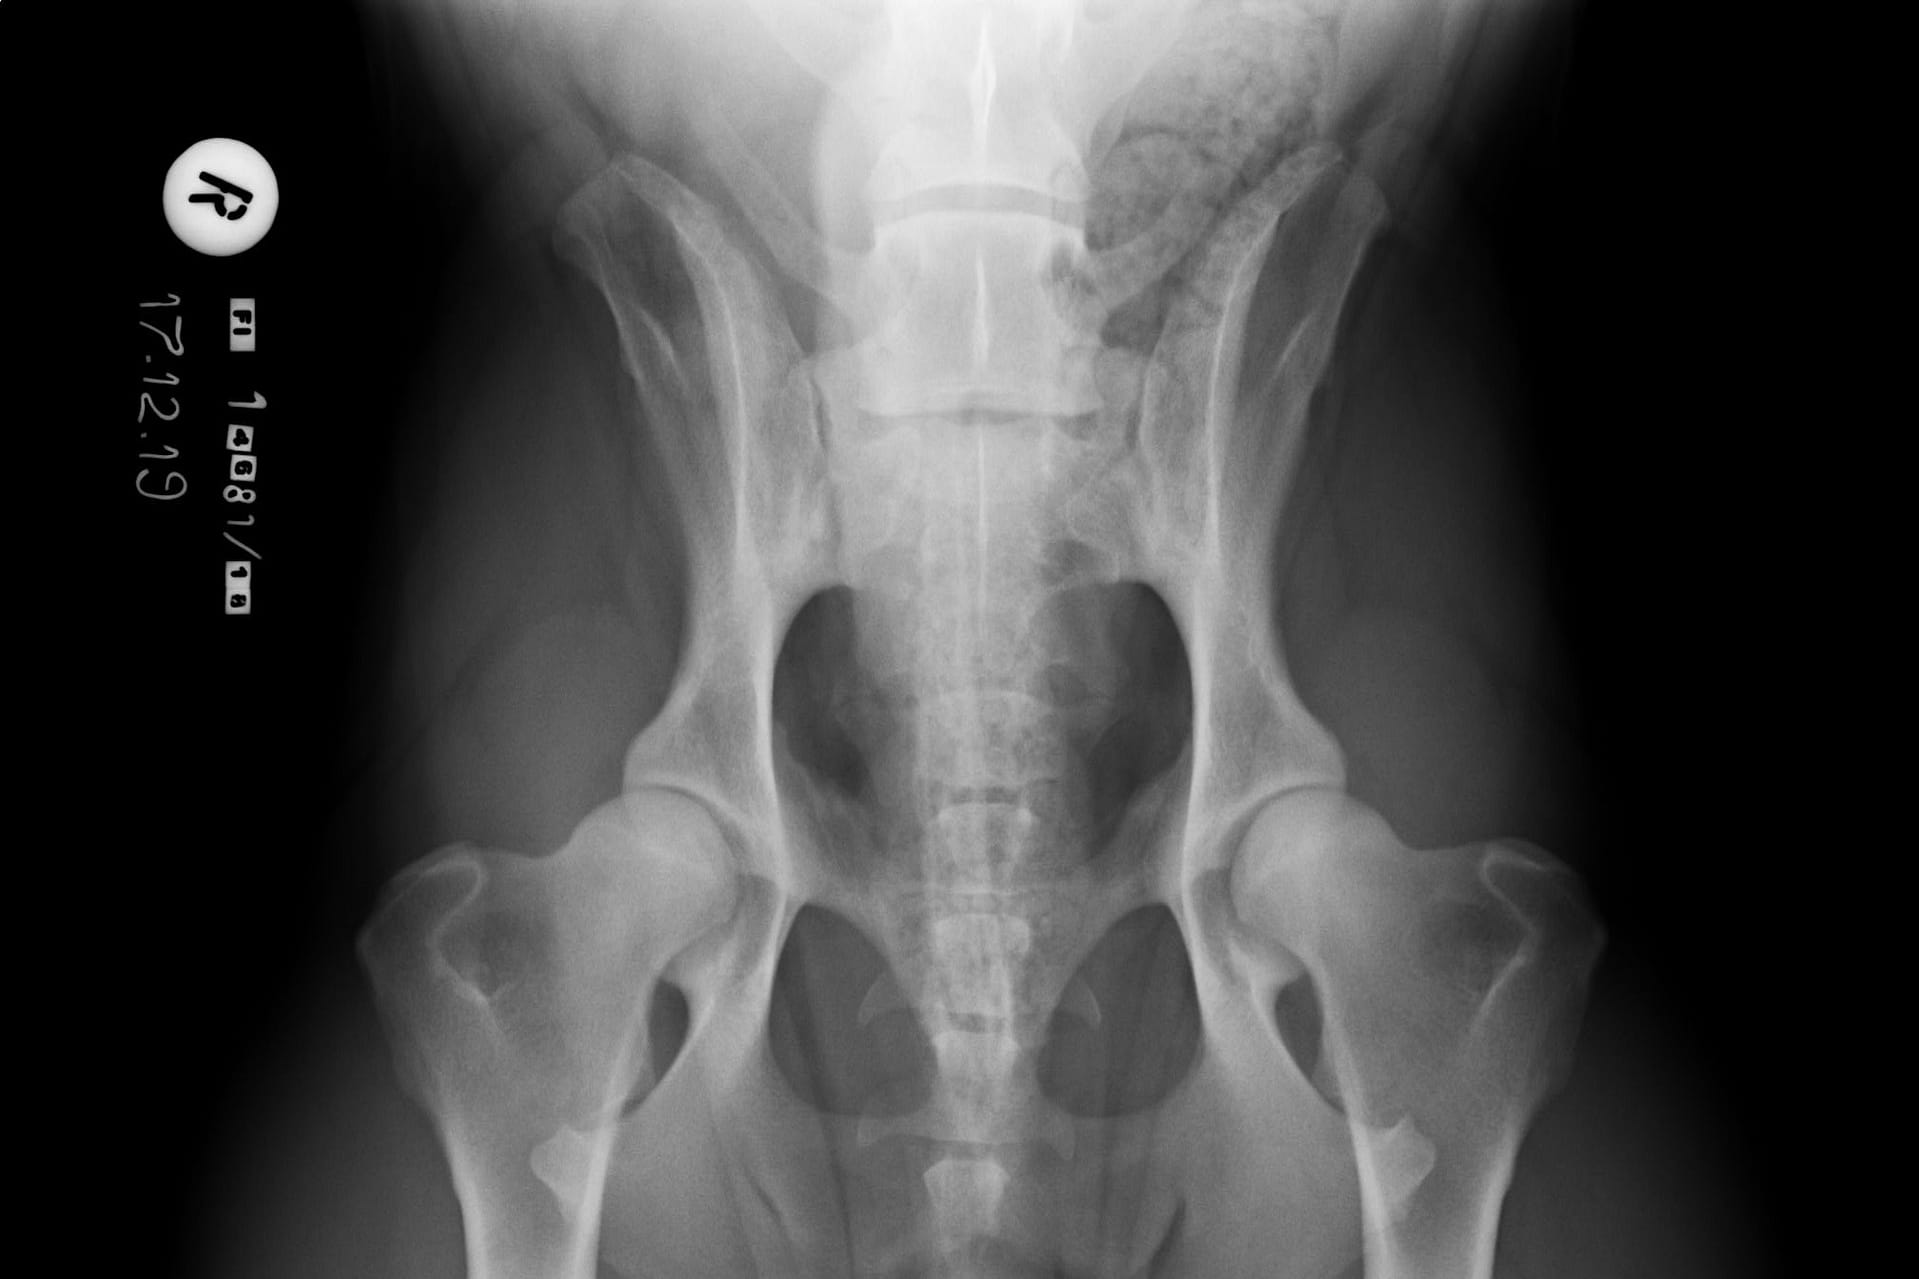

LTV2; symmetrical

The asymmetrical form, LTV3, seems to be a bit more tricky than the other forms. In some cases asymmetrical form comes with rotated pelvis, which might lead to unilateral development in hips. This is actually very logical; when the pelvis is not straight and in balance there will be uneven bear of weight between hips. In long term this uneven state might cause the worse hip wear sooner than the better hip and lameness and osteoarthritis may occur.

In the Finnish Kennel Club’s database 38,9% of Rhodesian Ridgebacks with LTV3 have one hip scored 1-2 degrees lower than the other one, ie. A/C (Oct 2020). The score doesn’t tell if the dog’s pelvis is straight or rotated.

“Asymmetrical LTV favours pelvic rotation over its long axis, resulting in inadequate femoral head coverage by the acetabulum on one side. Inadequate coverage of the femoral head favours subluxation, malformation of the hip joint, and secondary osteoarthritis. Asymmetrical hip conformation may therefore be the sequela of a LTV and mask or aggravate genetically induced canine hip dysplasia.”

(Flückiger M., Frank Steffen F. et al 2017)